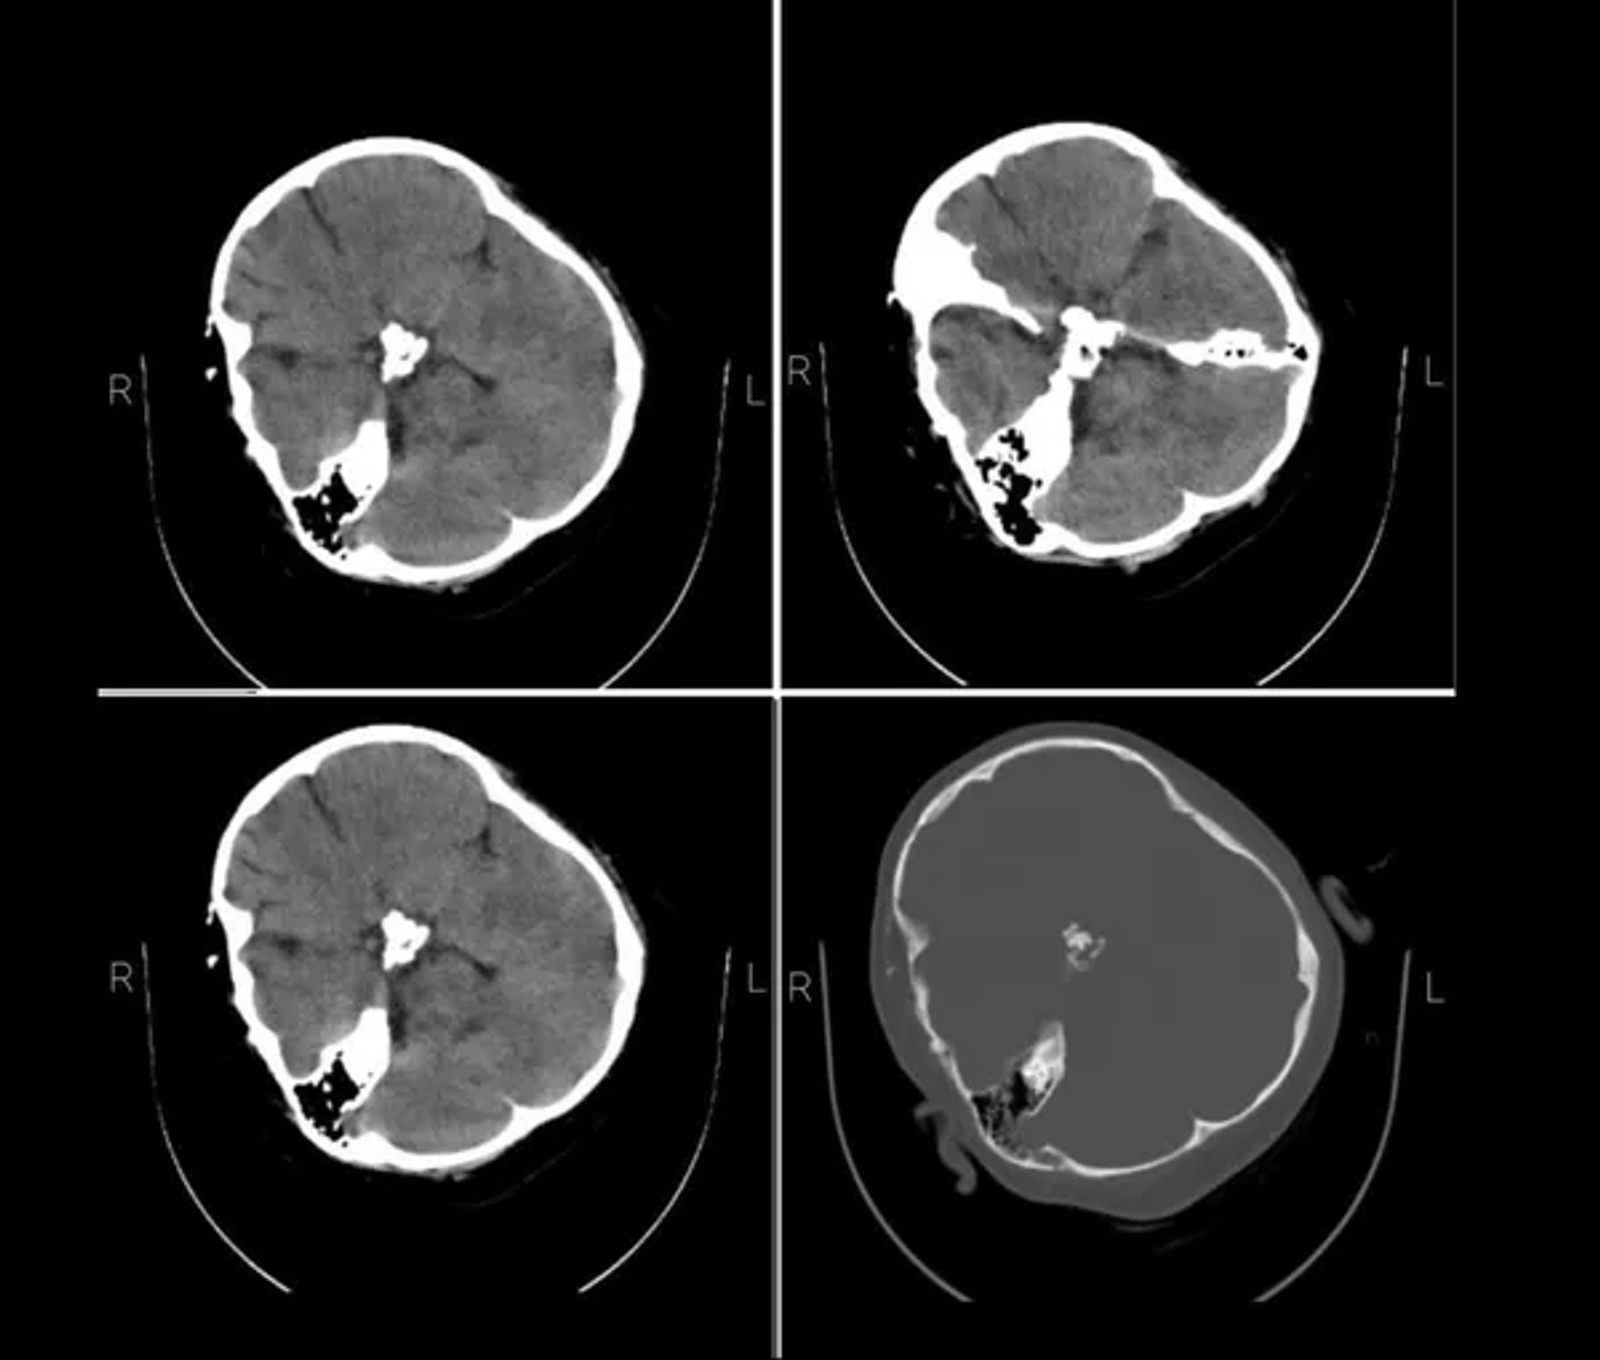

Doctors told Iran International earlier that all medical signs pointed to severe blows to Mahsa's head that fractured her skull, leading to a coma, and that they could not do anything to save her.